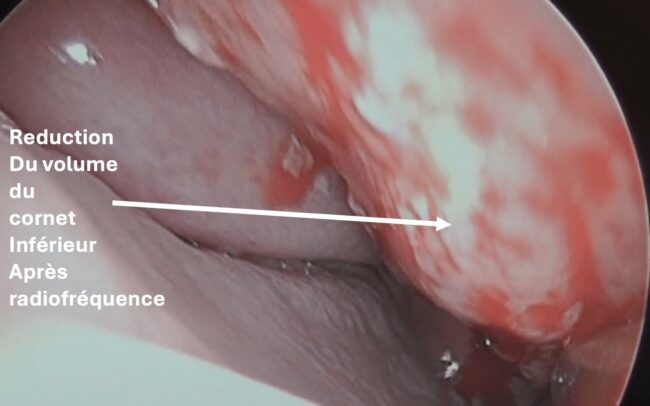

Hypertrophie des cornets

Les cornets sont des structures osseuses recouvertes de muqueuse qui peuvent augmenter de volume, notamment en cas d’allergies ou de sinusite chronique, rendant la respiration nasale difficile.

Les traitements sont les sprays nasaux à base de corticoïdes ou en cas d’échec du traitement médical, une réduction du volume des cornets par radiofréquence